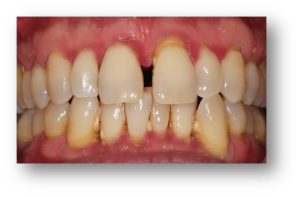

![]() | ![]() |

| Untreated severe gum disease | Gum disease treated and stabilised by Dr Halai |